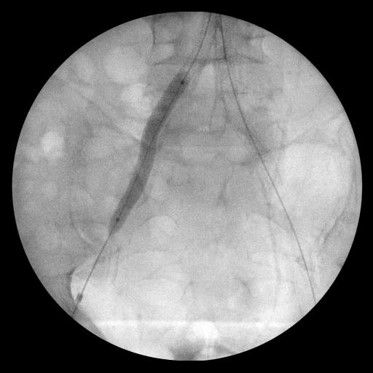

Непосредственный результат.

ЛПИ: 0,8/0,8